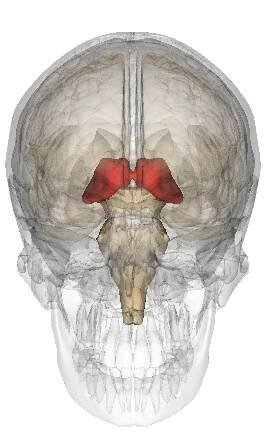

The thalamus (pl.: thalami; from Greek θάλαμος, "chamber") is a large mass of gray matter on the lateral wall of the third ventricle forming the dorsal part of the diencephalon (a division of the forebrain).

Thalamus je mozková struktura, která je součástí diencefala (mezimozek), a nachází se v blízkosti třetí mozkové komory. Má složitou strukturu, skládá se z řady jader a má komplexní funkce.

Thalamus (česky hrbol mezimozkový) je spolu s epithalamem součástí zadní části mezimozku (diencephalon) a je seskupením senzorických, asociačních a nespecifických jader. Zprostředkovává převod informací přicházejících z periférie do specifických projekčních a asociačních oblastí mozkové kůry a do důležitých center mozečku. Umožňuje také vzájemnou interakci vyšších oddílů CNS. Wikipedie